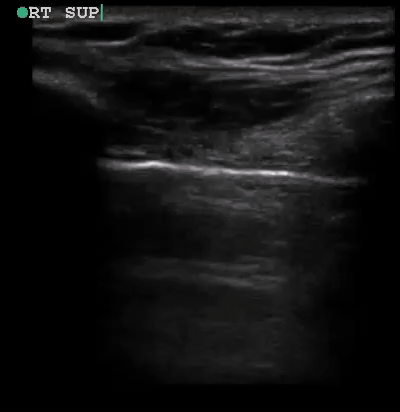

Pneumothorax is generally diagnosed by noting the sonographic absence of lung sliding, which will be present in 90-95% of pneumothoraces.5 Lung sliding is characterized by a shimmering to and fro appearance of the pleural line, sometimes referred to as “ants marching.” Frequently, bright hyperechoic vertical streaks, called comet tails or z-lines (see Figure 1), may be seen emanating from the pleural line and indicate the presence of lung sliding (i.e., no pneumothorax). A lung point is the visualization of the edge of a pneumothorax, where lung sliding and no lung sliding is seen in the same field of view. Sonographically, it is the point at which the visceral pleura has separated from the parietal pleura along the chest wall. This sign has a sensitivity of 60-66%, and is noted to be almost 100% specific.4,12

If it is difficult to visualize lung sliding, motion or M-mode can also be used to visualize movement of the pleura. Upon switching to M-mode, the ultrasound operator will position the M-mode line over the pleural line between two rib shadows (Video 4). M-mode is then activated, and plotted across the screen in one of two common patterns. The appearance of the “sky-ocean-beach” pattern indicates normal lung sliding and therefore no pneumothorax (see Figure 1). The appearance of a “sky-ocean-no beach” pattern, sometimes referred to as “barcode” or “stratosphere” sign, indicates the absence of lung sliding and therefore is indicative of a pneumothorax.